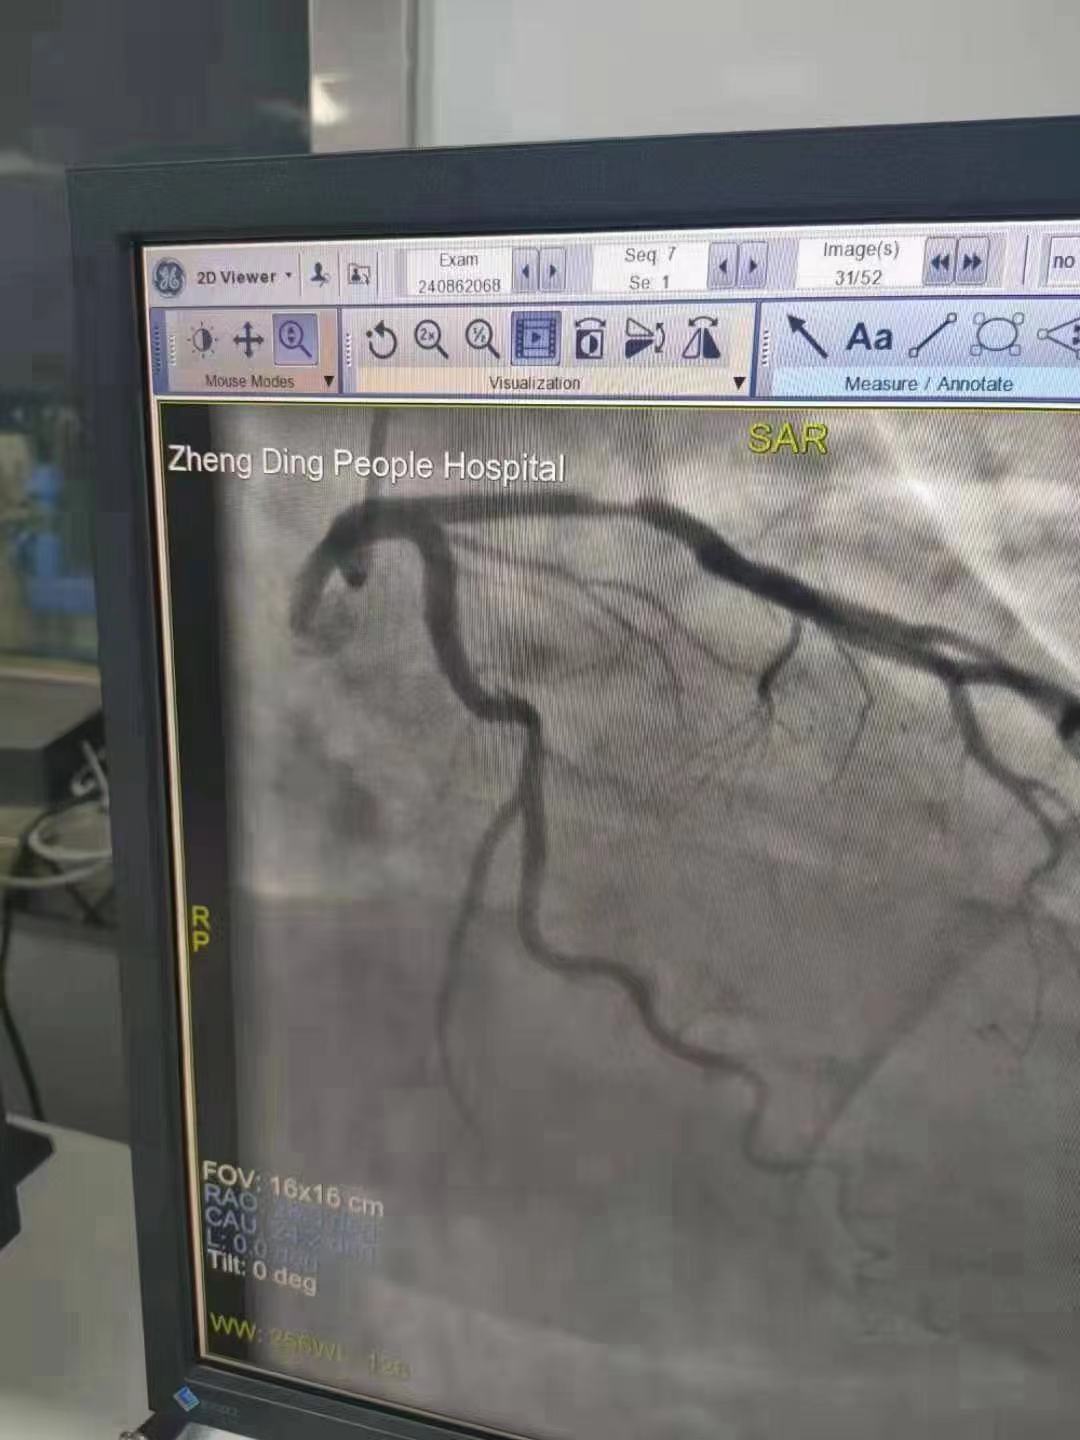

祝賀 正定縣醫(yī)院李京芳 主任團(tuán)隊成功為患者植入Xinsorb生物可吸收支架!